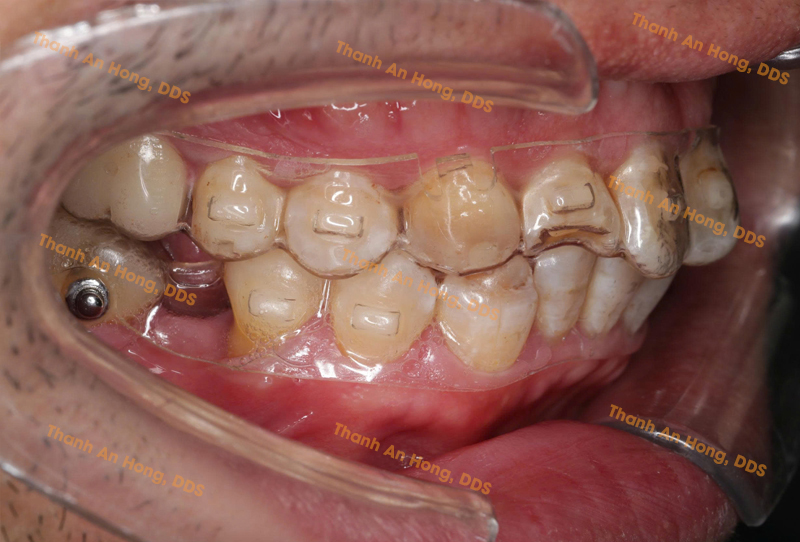

HÌNH ẢNH THỰC TẾ

Chỉnh khay dựng trục răng cối lớn hàm dưới